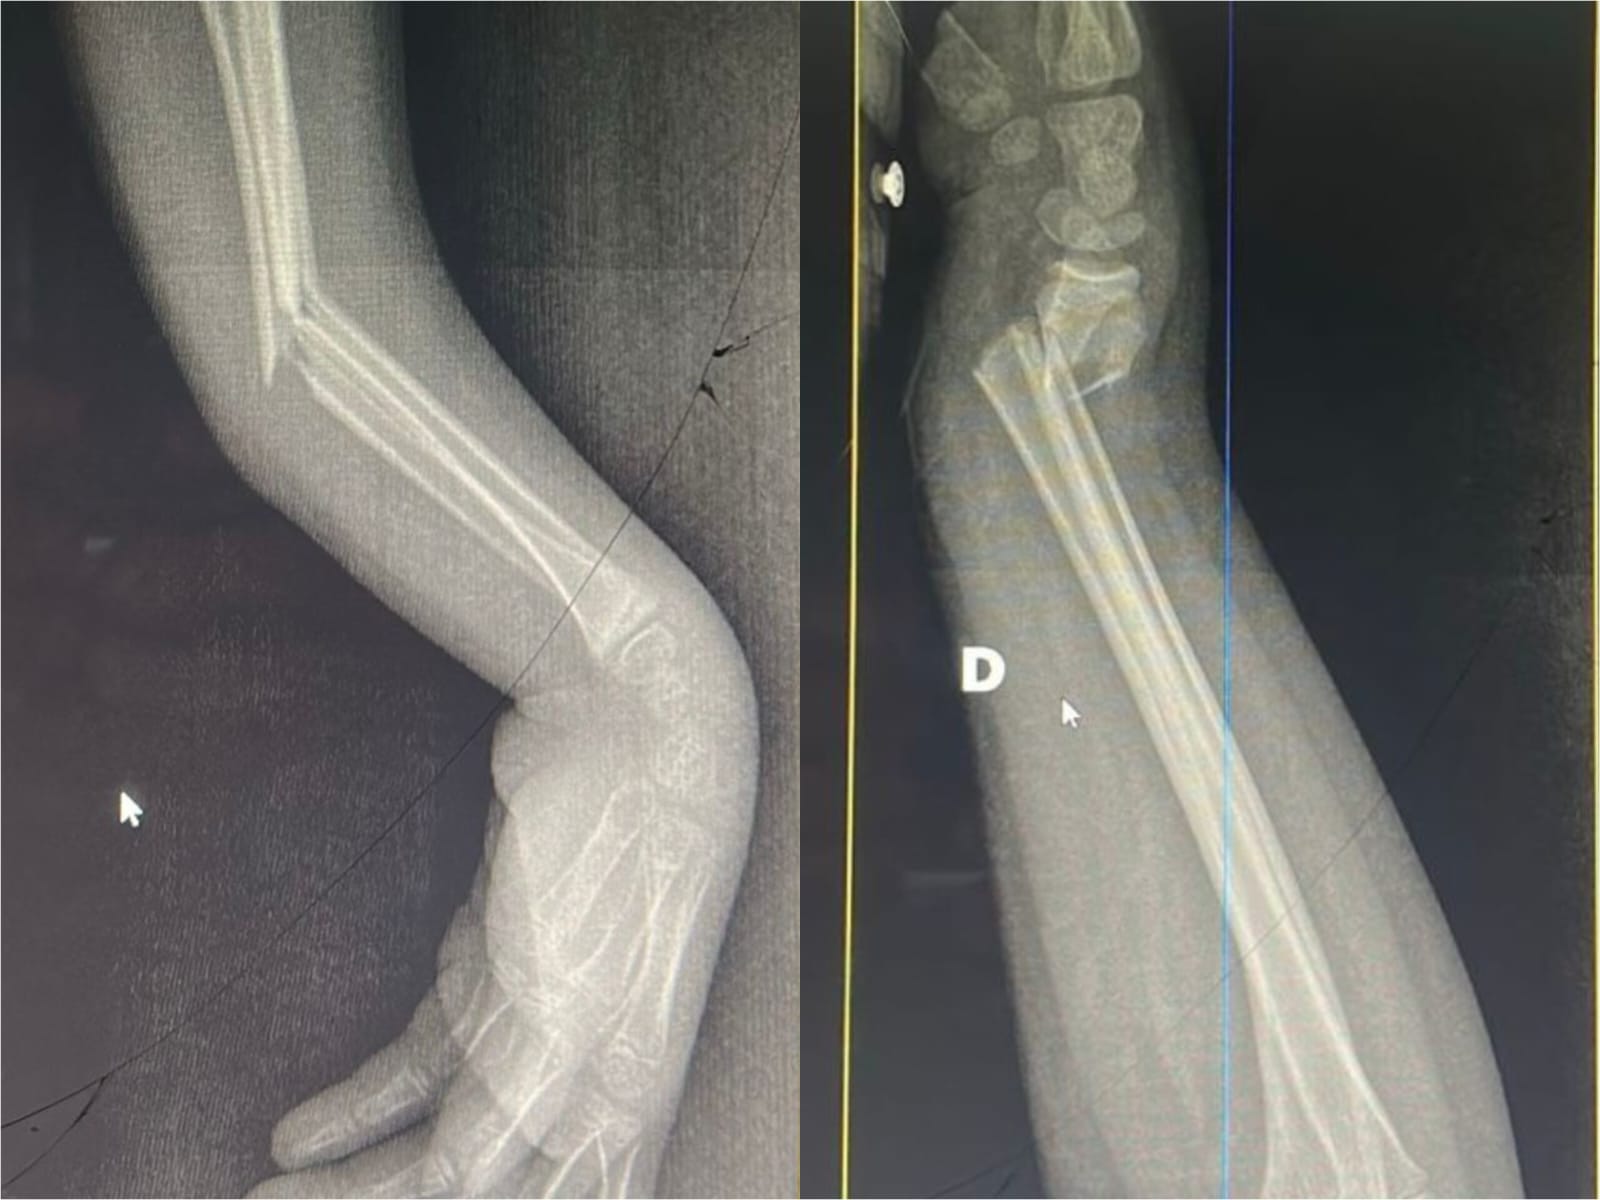

Essa transformação não está apenas nos números. Ela pode ser vista. As imagens que acompanham este texto mostram dois casos atendidos hoje no pronto socorro: crianças com fraturas no antebraço que foram avaliadas, diagnosticadas e operadas no próprio hospital, sem necessidade de transferência. Situações que exigem agilidade, equipe treinada e estrutura funcional.